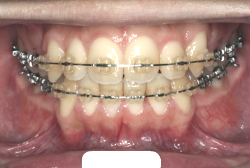

歯科矯正用アンカースクリューを用いた症例(骨格性反対咬合 非抜歯治療)

「ものがうまく噛めない」という主訴で来院したケースです。診断の結果、「骨格性反対咬合に伴う咬合不良+軽度叢生」と判明しました。原因としては特に下顎の左側が過成長したため、骨格性反対咬合になり、特に左側での噛み合わせが非常に悪くなっていると診断しました。初診時の写真を見ると、上下の正中線の大きなズレ、左側の噛み合わせの不良がはっきり分かります(黄色の矢印と緑の矢印は一致しているのが正しい状態です)。

そもそも、このような状態となっているのは骨の大きさに問題があるため生じていますので、場合によっては、「外科矯正」によって下顎の骨を外科的に縮めることで修正します。患者様が外科矯正をご希望されない場合は、従来ですと上下左右の小臼歯抜歯を行い矯正するのが普通です。

今回の患者様の場合は、「外科」も「小臼歯抜歯」も拒否されましたので、歯科矯正用アンカースクリュー(以下 アンカースクリュー)を用いて、下顎の歯列全体を後方に下げるという方法を取りました。

治療中の写真で、アンカースクリューより歯を後ろへ牽引しているのがお分かりいただけるかと思います。牽引を1年ほど続け、途中補助的に上下にゴムをかける(これを顎間ゴムと言います)手法なども追加し、全体で21ヶ月で治療を終えることが出来ました。

結局歯の本数を減らすことなく、すべてご自分の歯を残して、正しい配列と噛み合わせにすることができました。凸凹があまりひどくないため、簡単そうに見えると思いますが、このケースの初診の状態を見ると、熟練の矯正歯科医でも悩みのつきないケースです。まして、外科も出来ない、抜歯もイヤ、と言うことになると、従来の方法では治療不可能と考えられるのですが、アンカースクリューを使うことで最近は不可能が可能となってきました。